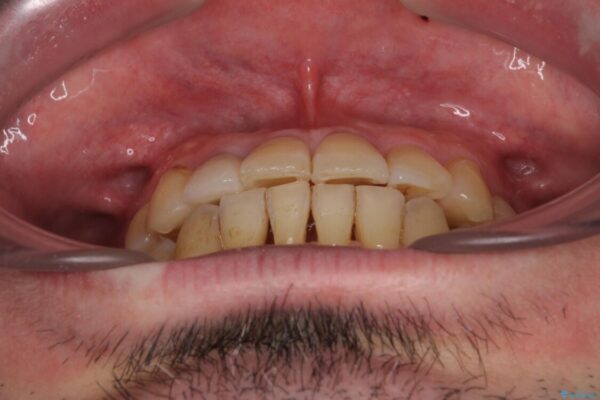

奥歯の痛みと前歯のデコボコを気にして来院された患者様です。

左右下顎の大臼歯は、ともに歯根が破折しており、抜歯が必要な状態でした。

放置したことで炎症による骨吸収が顕著であるため、骨造成を併用してインプラント埋入を行うこととしました。

咬み合わせは受け口傾向であり、上顎前歯の叢生が顕著であったことから、第1小臼歯抜歯による矯正治療も検討しましたが、下顎大臼歯を左右ともに抜歯するため、非抜歯による矯正治療を行うこととしました。

治療前